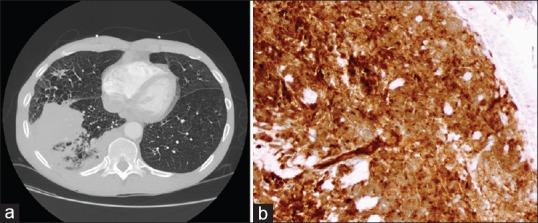

Pulmonary lymphoproliferative neoplasms are rare lung tumors and account for <1% of all lung tumors. Among them, primary pulmonary lymphomas (PPL) constitute the majority, which include Non-Hodgkin's lymphoma (NHL) that comprise of mucosa-associated lymphoid tissue lymphoma, diffuse large B-cell lymphomas and other rare types of NHL and lymphomatoid granulomatosis. HL, which arises secondary to contiguous spread from the mediastinum, is the rarest type of PPL. Other entities described within the umbrella of pulmonary lymphoproliferative neoplasms include pleural lymphomas and posttransplant lymphoproliferative disorders (PTLD) - which occurs in the poststem cell and organ transplant patients. These neoplasms although rare, have a favorable prognosis, which does not depend on disease resectability. Moreover, with its nonspecific presentation, diagnosis is challenging, which often leads to delayed diagnosis or misdiagnosis in many cases. Therefore, knowledge of this entity is important for the practicing pulmonologist. This review article aims to describe the clinical presentation, diagnosis and management of primarily the entities within PPL, as well as pleural lymphomas and PTLD.

肺淋巴增殖性肿瘤是罕见的肺部肿瘤,占所有肺部肿瘤的比例不到1%。其中,原发性肺淋巴瘤(PPL)占大多数,包括非霍奇金淋巴瘤(NHL),后者由黏膜相关淋巴组织淋巴瘤、弥漫性大B细胞淋巴瘤以及其他罕见类型的NHL和淋巴瘤样肉芽肿组成。HL是PPL中最罕见的类型,它继发于纵隔的连续性扩散。肺淋巴增殖性肿瘤范畴内描述的其他实体包括胸膜淋巴瘤和移植后淋巴增殖性疾病(PTLD)——发生于干细胞和器官移植后的患者。这些肿瘤虽然罕见,但预后良好,其预后并不取决于疾病的可切除性。此外,由于其表现不具有特异性,诊断具有挑战性,这在许多情况下常常导致诊断延迟或误诊。因此,了解这一实体对执业肺科医生很重要。这篇综述文章旨在描述主要是PPL内的实体以及胸膜淋巴瘤和PTLD的临床表现、诊断和管理。